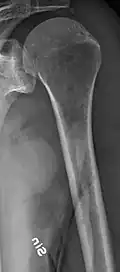

The diagnostic examination of a person with suspected multiple myeloma typically includes a skeletal survey. This is a series of X-rays of the skull, axial skeleton, and proximal long bones. Myeloma activity sometimes appears as "lytic lesions" (with local disappearance of normal bone due to resorption) or as "punched-out lesions" on the skull X-ray ("raindrop skull"). Lesions may also be sclerotic, which is seen as radiodense.[76] Overall, the radiodensity of myeloma is between −30 and 120 Hounsfield units (HU).[77] Magnetic resonance imaging is more sensitive than simple X-rays in the detection of lytic lesions. An MRI may supersede a skeletal survey, especially when vertebral disease is suspected. Occasionally, a CT scan is performed to measure the size of soft-tissue plasmacytomas. Nuclear Medicine Bone scans are typically not of any additional value in the workup of people with myeloma (no new bone formation; lytic lesions not well visualized on nuclear bone scan).

Bone pain affects almost 70% of people with multiple myeloma and is one of the most common symptoms.[2]: 653 [23] Myeloma bone pain usually involves the spine and ribs and worsens with activity. Persistent, localized pain may indicate a pathological bone fracture. Involvement of the vertebrae may lead to spinal cord compression or kyphosis. Myeloma bone disease is due to the overexpression of receptor activator for nuclear factor κ B ligand (RANKL) by bone marrow stroma. RANKL activates osteoclasts, which resorb bone. The resultant bone lesions are lytic (cause breakdown) in nature. They are best seen in plain radiographs, which may show "punched-out" resorptive lesions (including the "raindrop" appearance of the skull on radiography). The breakdown of bone also leads to the release of calcium ions into the blood, leading to hypercalcemia and its associated symptoms.[24]